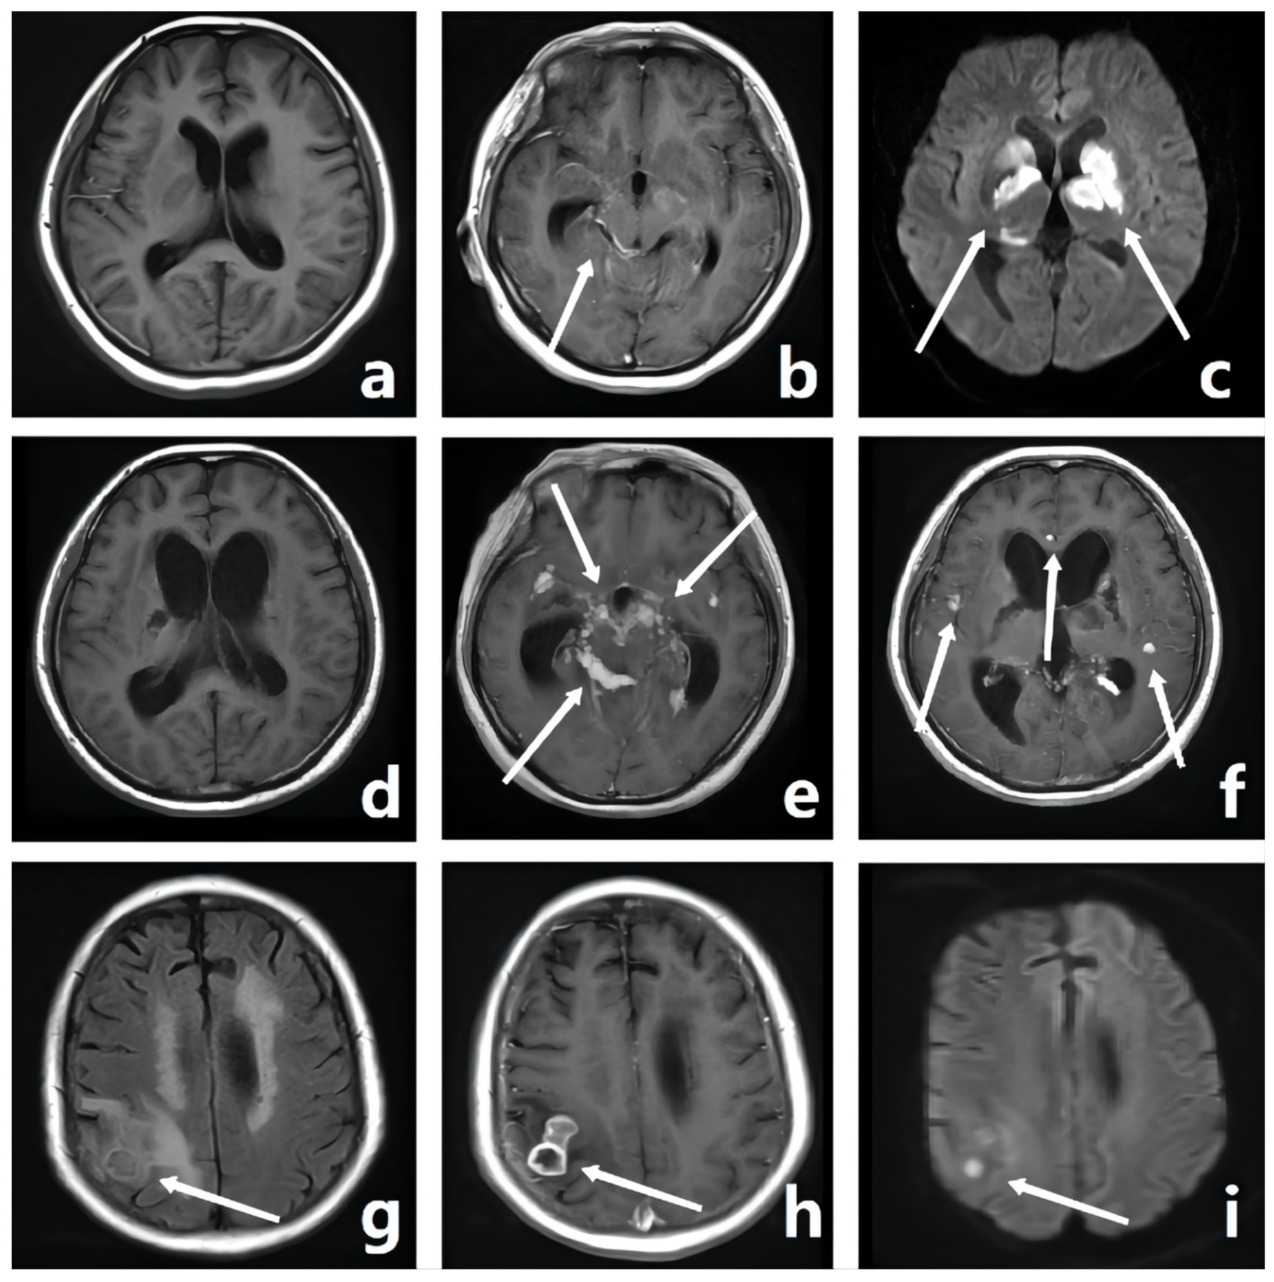

| Tuberculoma | Nodules with equal or slightly low signal intensity | The liquefaction part of the nodule shows high signal intensity, and the non-liquefied caseous necrosis part shows low signal intensity | The liquefaction part of the nodule center shows low signal intensity, the non-liquefied caseous necrosis part shows equal signal intensity, and the tumor wall shows high signal intensity | Low signal intensity | Uniform or circular enhancement | Location: frontal lobe, parietal lobe, temporal lobe, occipital lobe, corpus callosum, basal ganglia, cerebellum, brain stem, and meninges Is the lesion diffuse? |

| ACI | Low signal intensity | High signal intensity | High signal intensity | High signal intensity | Enhanced lesion area | Location: frontal lobe, parietal lobe, temporal lobe, and occipital lobe Volume of infarcted brain tissue |

| OCI | Low signal intensity | High signal intensity | Low signal intensity | Low signal intensity | No enhancement in lesion area | Location: frontal lobe, parietal lobe, temporal lobe, and occipital lobe |

| Abscess | The abscess cavity shows low signal intensity, and the abscess wall shows equal signal intensity | The abscess cavity shows high signal intensity, and the abscess wall shows slightly high signal intensity | The abscess cavity shows slightly low signal intensity, and the abscess wall shows slightly high signal intensity | The abscess cavity shows high signal intensity | The abscess wall shows obvious circular enhancement | Does the patient have a brain abscess? |